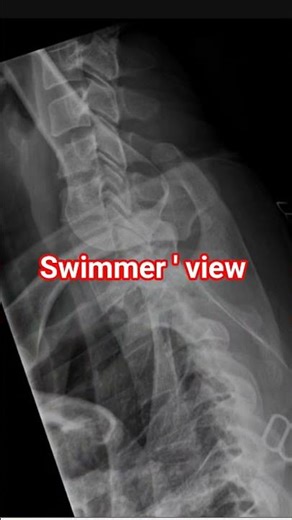

SWIMMER 'S VIEW || C-SPINE SWIMMER 'S LATERAL VIEW

What is Swimmer's View X-ray? How do you do a Swimmers X-ray? Swi

Cervicothoracic (SWIMMER'S) Lateral Position

X-RAY Cervico -Thoracic vertebrae Lateral swimmers View C7 D1 #sw

Rad Tech Lab: C-spine: Swimmers View